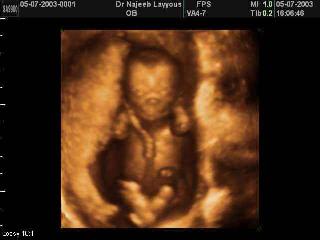

Does abortion and only a “potential” life? These medical textbooks and scientists claim that life begins at conception, which means that an actual life and not a potential life is what is ended in an abortion.